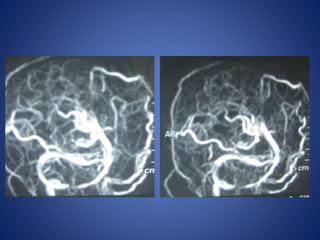

5 yrs male child with history of left sided focal seizures with secondary generalization

5 yrs malechild with history of left sided focal seizures with secondary generalization

Moya Moya • Chronicprogressive arteriopathy of unknown cause and has become one of the most common causes of pediatric stroke. • Suzuki and Kodama classified the evolution of moyamoya disease using angiographic findings to define six phases of the disease: Stage 1- Narrowing of carotid fork. Stage 2- Initiation of basal moyamoya. Stage 3- Intensification of moyamoya Stage 4- Minimization of moyamoya. Stage 5- Reduction of moyamoya . Stage 6- Disappearance of moyamoya.

• Stenosis/occlusion ofthe distal ICA • moyamoya vessels with signal voids in the basal ganglia • ischemia • infarction • atrophy, and ventriculomegaly. • Small abnormal net-like vessels proliferate giving "puff of smoke" appearance. • Contrast-enhanced T1WI - marked leptomeningeal enhancement along the cortical sulci (ivy sign). often show contrast stagnating in slow-flowing collateral vessels both in the brain parenchymal and over its surface. MR imaging